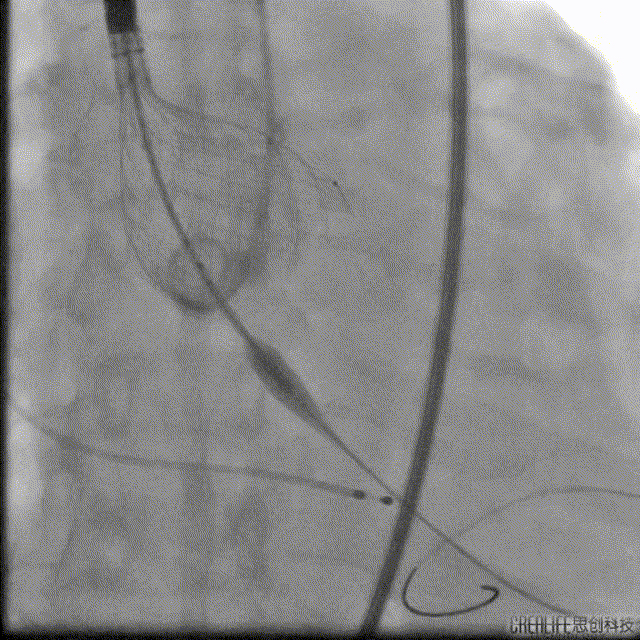

Venus32回收

VenusAplus32释放